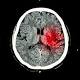

Princess Diana’s former lover James Hewitt suffers heart attack and … 9news.com.au Princess Diana’s former lover James Hewitt is reportedly in a critical condition after suffering a severe heart attack and stroke. Mr Hewitt had fallen ill two weeks ago before suffering a major heart attack and then a stroke, The Mirror reports … James Hewitt ‘suffered a heart attack and ... |